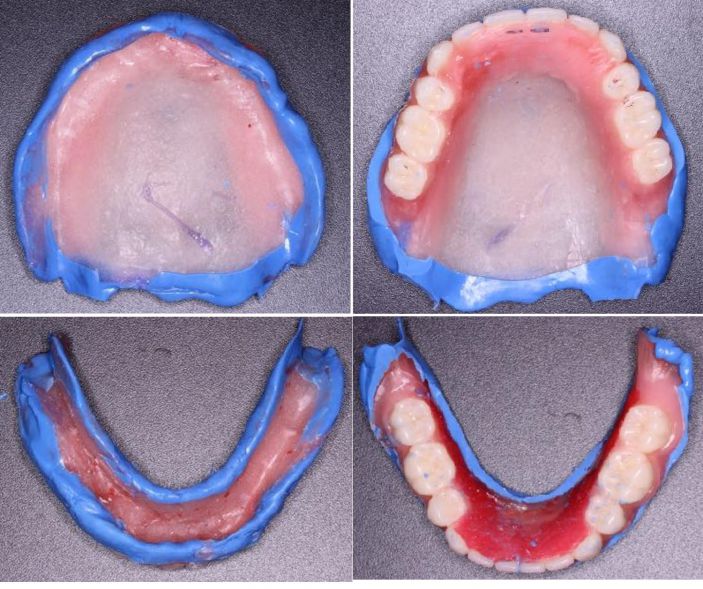

二、初印模

五、試排牙後行邊緣整塑

六、終印模

七、充膠、戴牙